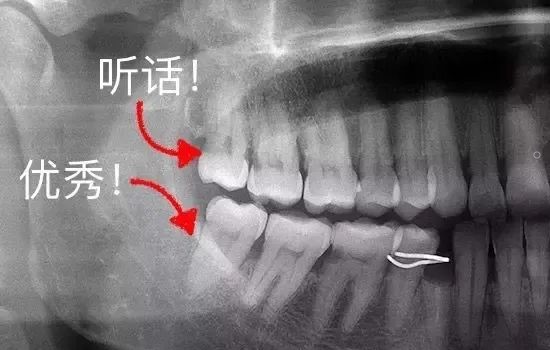

不过,也有一些特别乖的智齿,整整齐齐长出来,上下可以完美咬合,也没有什么蛀牙,平时都能刷干净。那么,这种优秀、听话的智齿完全可以留下,成为我们咀嚼食物的工具!